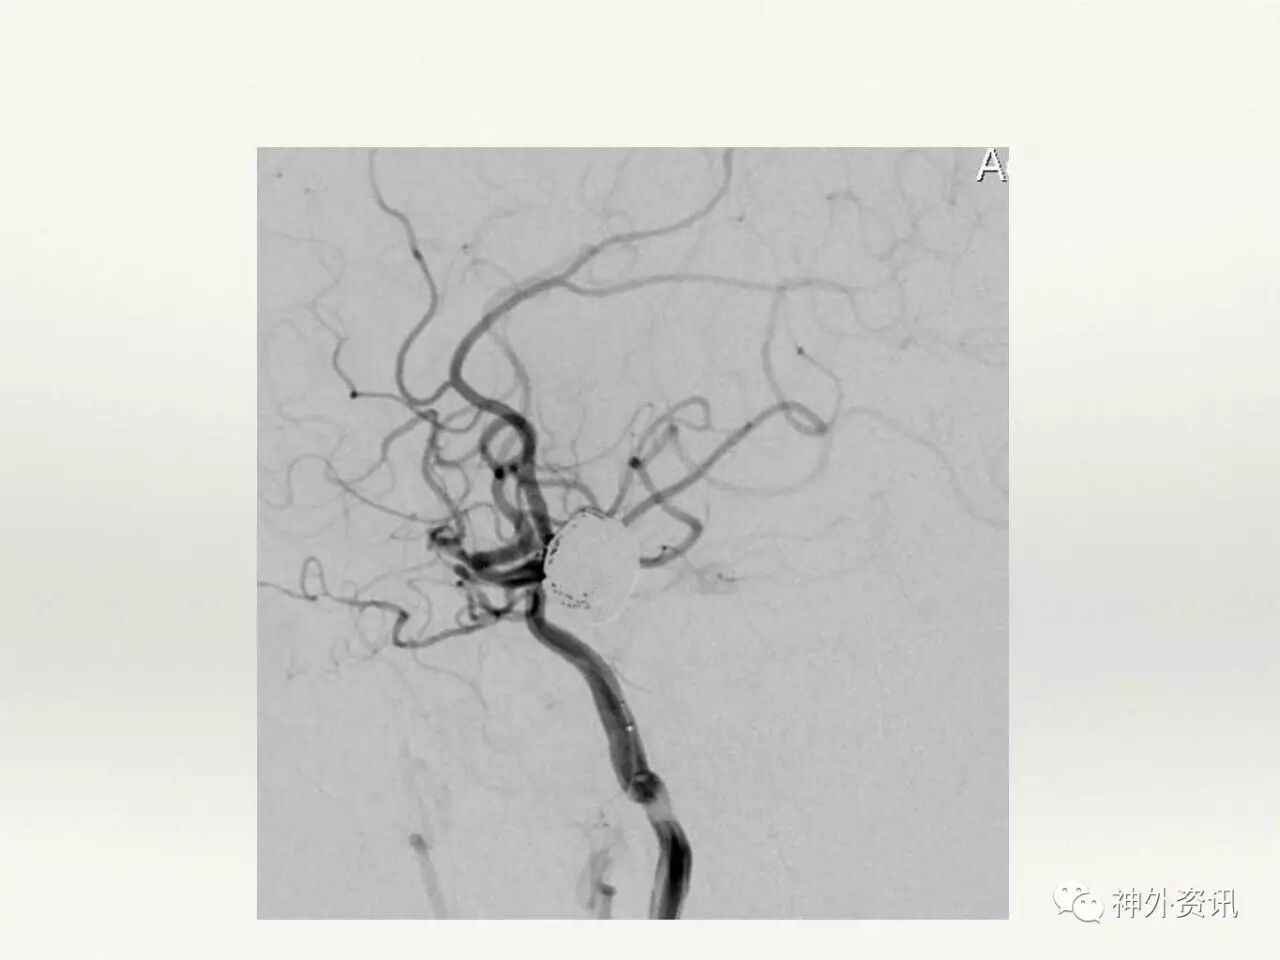

在东北地区率先开展了颈内动脉、大脑中动脉及基底动脉闭塞血管内再通、颅内动脉栓塞急性期取栓、血流导向装置治疗大型宽颈动脉瘤等,对颅内动脉瘤、动静脉畸形、颈动脉及颅内动脉狭窄、颈内动脉海绵窦瘘、硬脑膜动静脉瘘等外科治疗具有较深的造诣。完成脑血管造影8600余例,各类脑血管病介入手术共4500余例,动脉瘤、动静脉畸形、脑肿瘤、脑出血及脑外伤等外科手术1500余例。